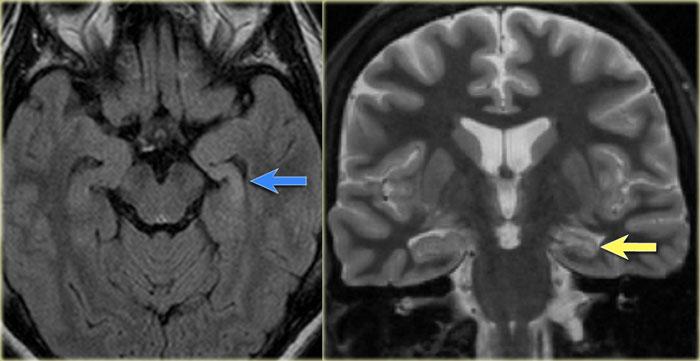

Hình ảnh T2W và FLAIR mặt phẳng coronal cho thấy xơ cứng thùy thái dương trong bên phải.

Lưu ý tình trạng mất thể tích, biểu hiện của teo não, gây giãn thứ phát sừng thái dương của não thất bên.

Tín hiệu cao trong hải mã phản ánh tình trạng gliosis.

Xơ cứng thùy thái dương trong bên trái. Gliosis kín đáo của hải mã trái (mũi tên xanh dương) và teo não (mũi tên vàng).

Bệnh nhân 35 tuổi với động kinh thùy thái dương kháng trị.

MRI cho thấy tăng tín hiệu kín đáo của hải mã trái trên chuỗi xung FLAIR axial (mũi tên xanh dương) và teo hải mã trái trên hình ảnh coronal (mũi tên vàng).

Bệnh nhân được điều trị thành công bằng phẫu thuật cắt hạnh nhân – hải mã bên trái.